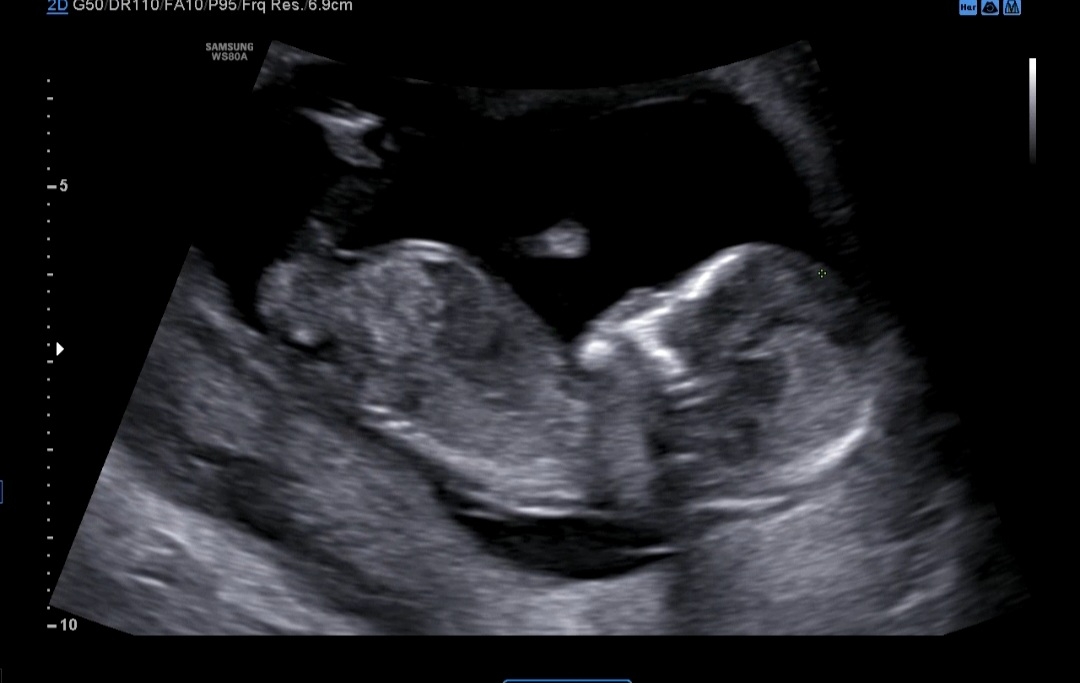

12주차 초음파 성별예측

아들일까요 딸일까요?

아들이용

각도가 아들인가보네요!

아들용